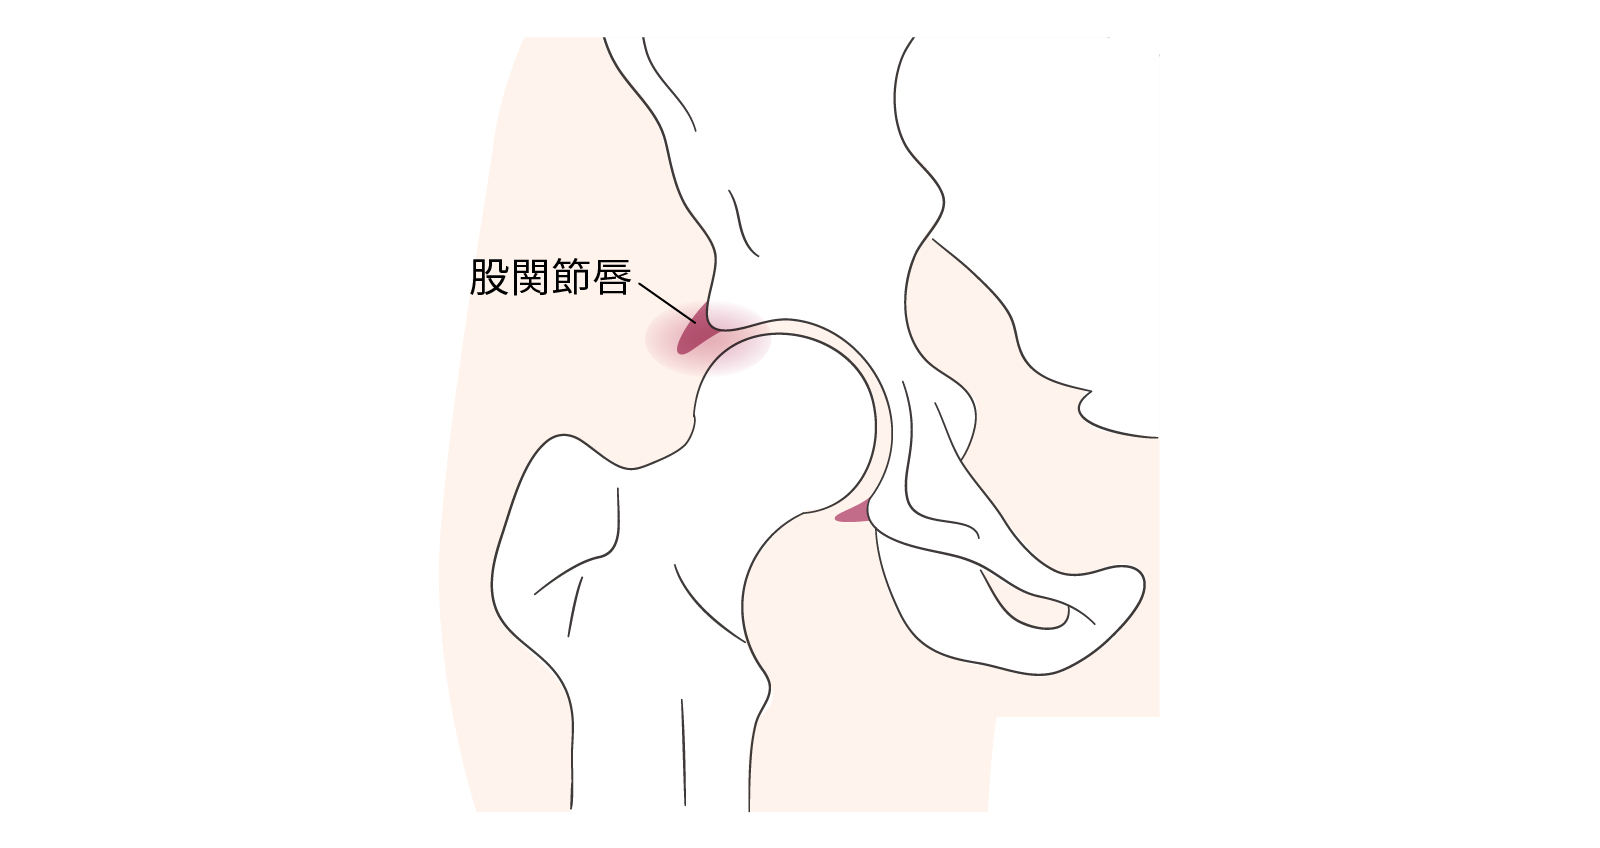

股関節唇損傷

こかんせつしんそんしょう

股関節唇損傷は、股関節の受け皿(臼蓋)の縁にくちびるのようにつく軟骨組織「関節唇」が傷つく病気で、主に成長期にできる大腿骨の変形(カム変形)が原因です。股関節を繰り返し曲げる動作で負荷がかかり、痛みや引っかかり感、可動域の制限が現れます。進行すると変形性股関節症に至ることもあります。